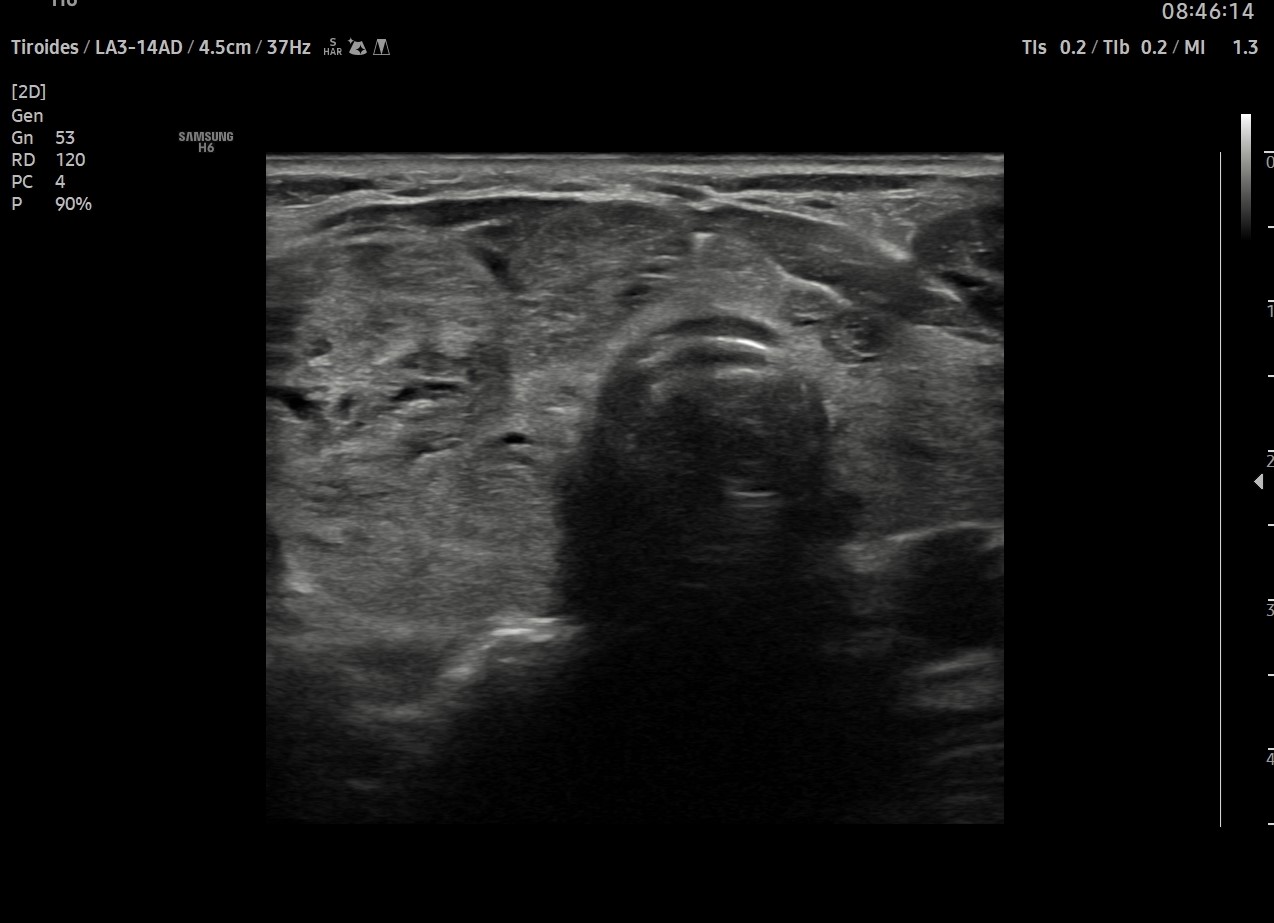

Ecografía tiroidea

Tiroides prácticamente ocupado en su totalidad por múltiples nódulos, el mayor en LTD, de aproximadamente 2,8 cm con una calcificación en su zona central (Tirads 4) (ya realizada PAAF previa)

El resto de tiroides muestra una ecogencidad desestructurada. Vascularización normal.

ID. Bocio multinodular.

Nódulo tirads 4 (PAAF previa)

Afectación marcada de la ecogenicidad probablemente por tiroiditis.